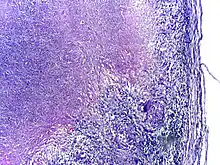

Using histological stains on expectorated samples from phlegm (also called sputum), scientists can identify MTB under a microscope. Since MTB retains certain stains even after being treated with acidic solution, it is classified as an acid-fast bacillus.[13][57] The most common acid-fast staining techniques are the Ziehl–Neelsen stain[59] and the Kinyoun stain, which dye acid-fast bacilli a bright red that stands out against a blue background.[60] Auramine-rhodamine staining[61] and fluorescence microscopy[62] are also used.

Tuberculosis is classified as one of the granulomatous inflammatory diseases. Macrophages, epithelioid cells, T lymphocytes, B lymphocytes, and fibroblasts aggregate to form granulomas, with lymphocytes surrounding the infected macrophages. When other macrophages attack the infected macrophage, they fuse together to form a giant multinucleated cell in the alveolar lumen. The granuloma may prevent dissemination of the mycobacteria and provide a local environment for interaction of cells of the immune system.[94]

However, more recent evidence suggests that the bacteria use the granulomas to avoid destruction by the host's immune system. Macrophages and dendritic cells in the granulomas are unable to present antigen to lymphocytes; thus the immune response is suppressed.[95] Bacteria inside the granuloma can become dormant, resulting in latent infection. Another feature of the granulomas is the development of abnormal cell death (necrosis) in the center of tubercles. To the naked eye, this has the texture of soft, white cheese and is termed caseous necrosis.[94]